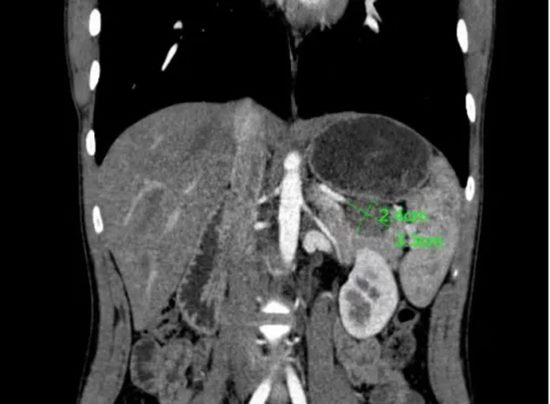

了解患者及家属的诉求后,陈艳军主任医师团队认真研读影像学资料,发现肿瘤位于胰腺尾部,紧邻脾门,与脾动脉、脾静脉关系密切。团队经过多方考量、反复讨论,最终决定为患者实施保留脾脏动静脉的保脾胰体尾切除术(Kimura手术)。

手术方式虽已确定,但对于一名16岁的孩子而言,一次胰腺手术不仅关乎生命安全,更关乎未来数十年的生长发育与生活质量。肿瘤紧邻脾脏、紧贴脾动静脉,病灶位置险要,解剖层次复杂,操作空间极小。稍有不慎,便可能损伤血管,导致术中出血或被迫切除脾脏。